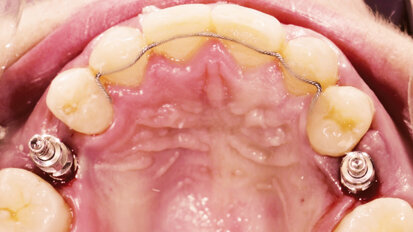

Nepřímá metoda pro ošetřování prostřednictvím provizorií

Týmový přístup při celkové hybridní rekonstrukci.